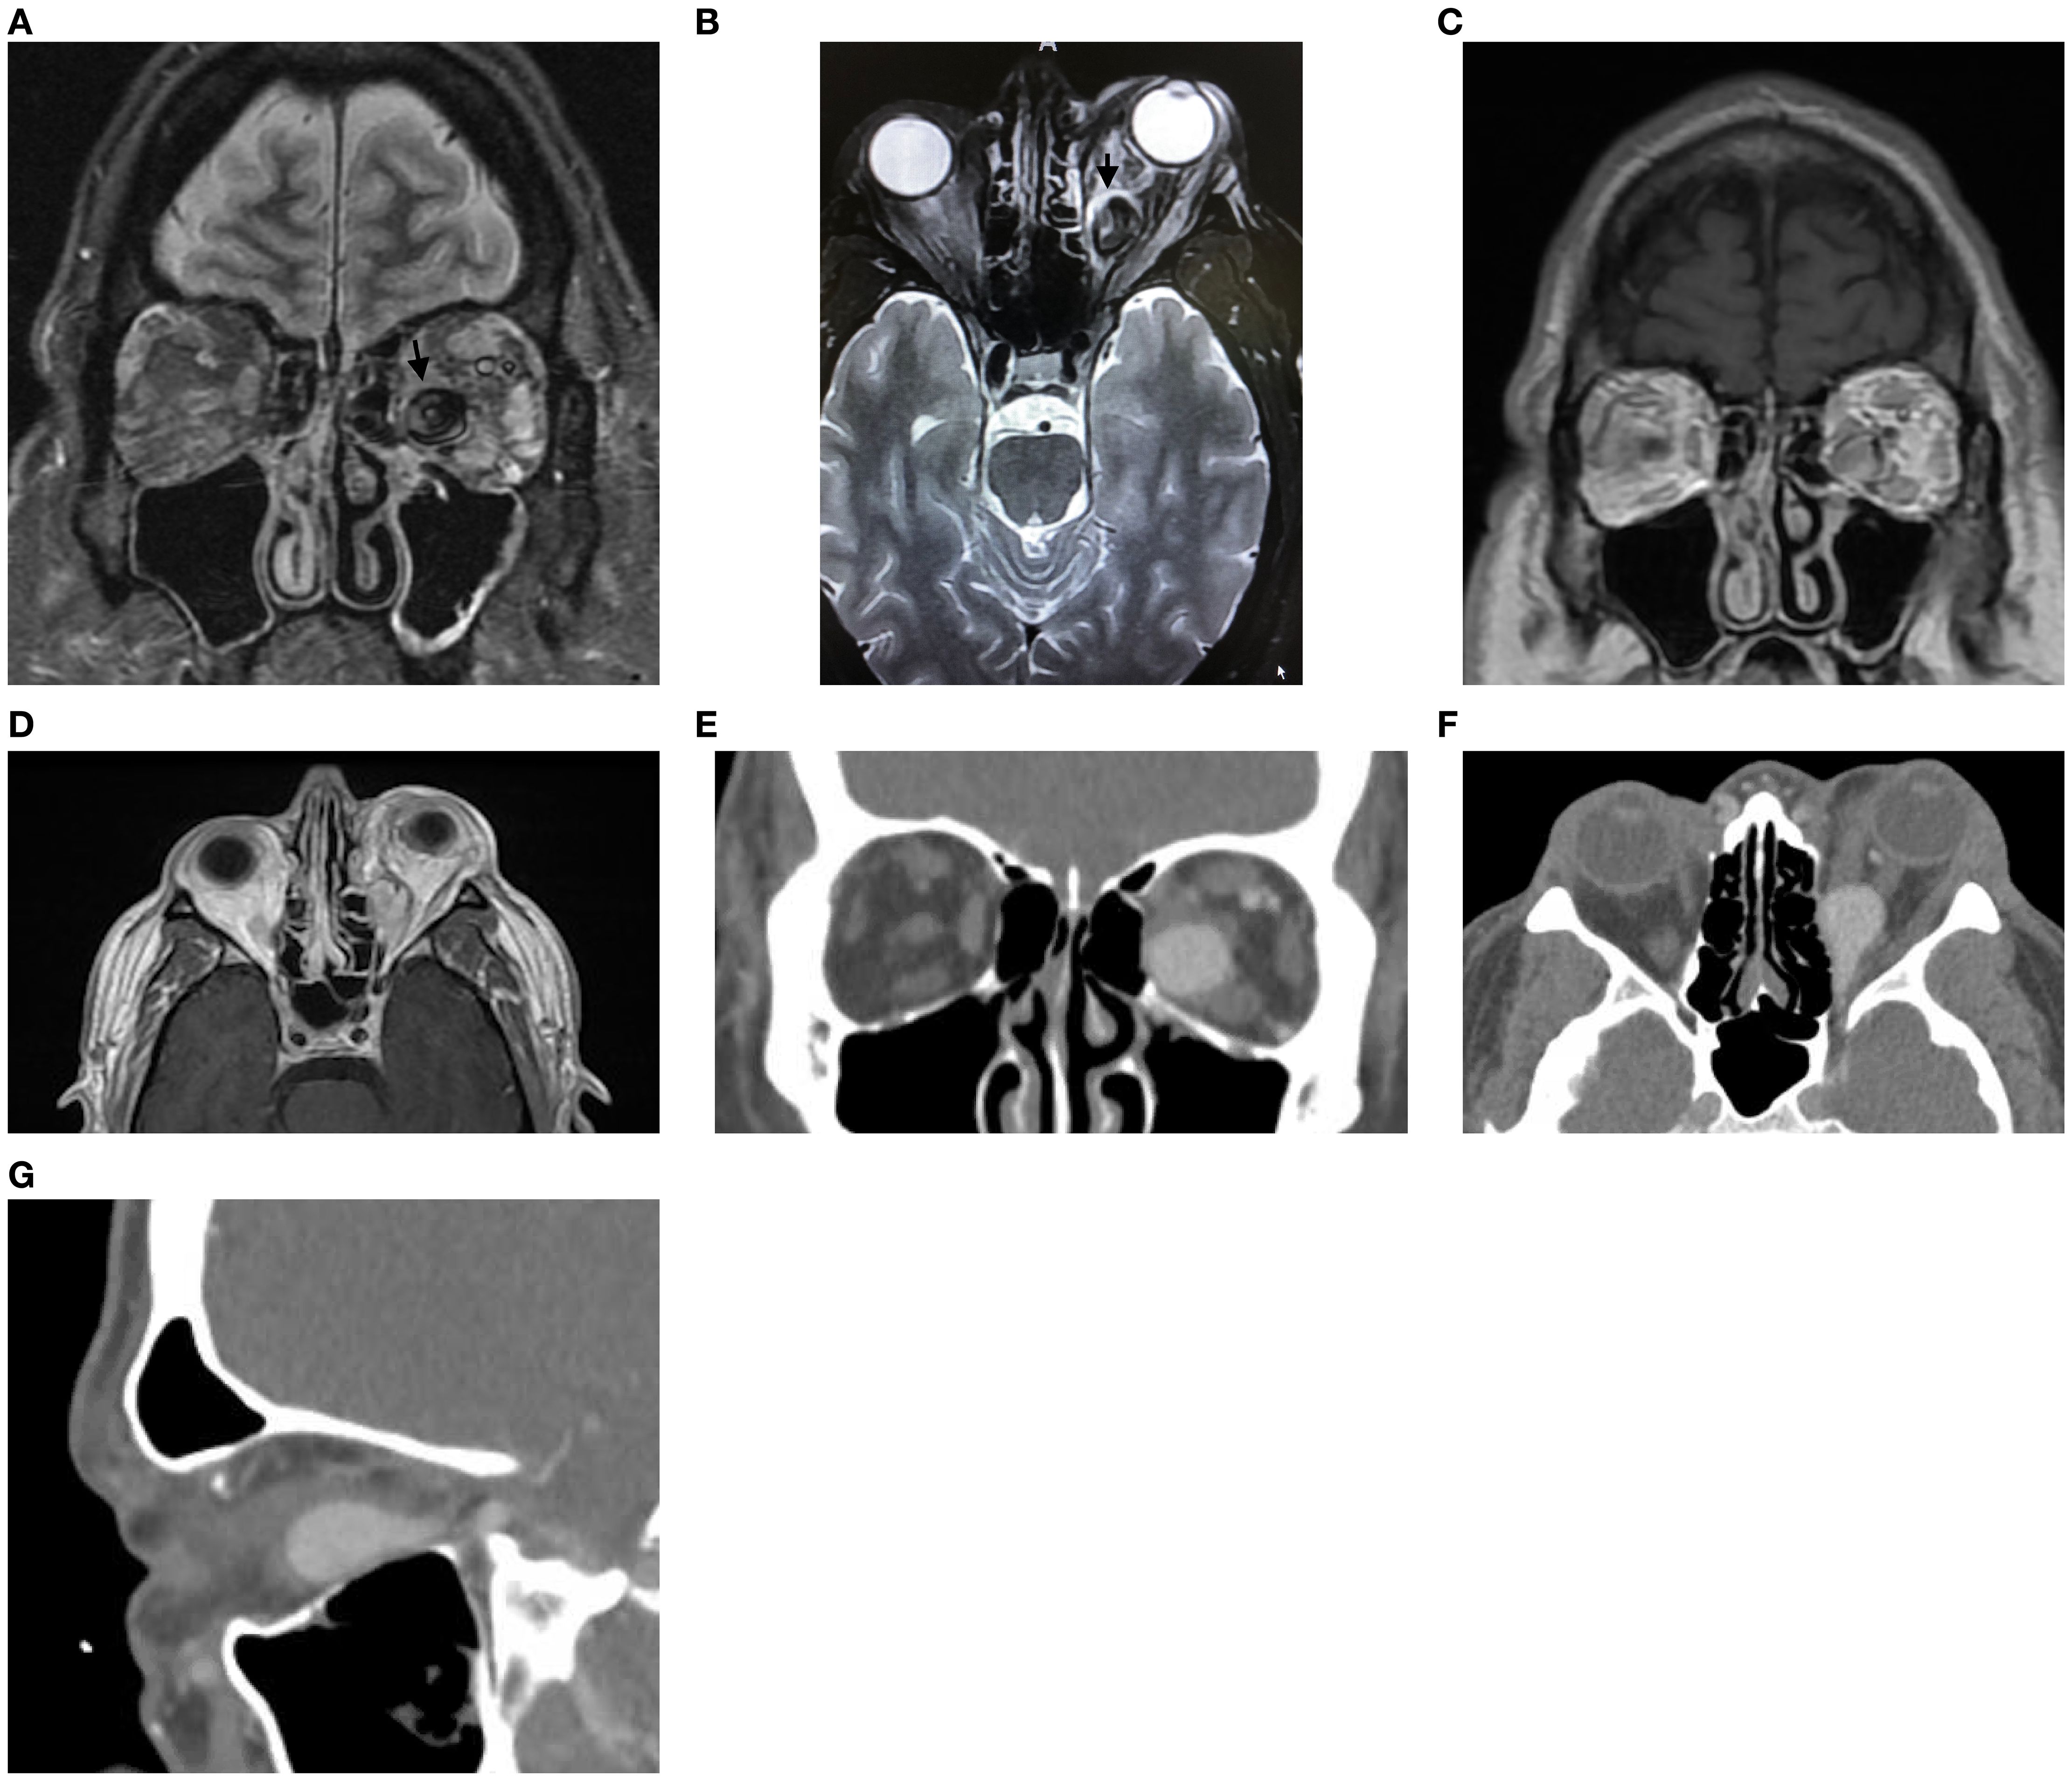

An angiographic image of cerebral arteries showing the internal carotid artery and its branches. Two small arrows indicate abnormal arterioles. The image highlights vascular pathways in the orbit.

Figure 3. Lateral view of the angiogram after internal carotid artery injection demonstrating feeding arterioles off the proximal ophthalmic artery (arrows).

A 48-year-old man presented with 1 month of blurry vision in the left eye without a history of trauma. His past medical history was significant for thyroid cancer in remission and hypothyroidism. On presentation to outside ophthalmology, he was noted to have left optic neuropathy with decreased vision (20/100), poor color vision, relative afferent pupillary defect, restricted extraocular motility, chemosis, eyelid edema, and elevated intraocular pressure. He had 5 mm of left-sided relative proptosis on Hertel exophthalmometry. Imaging, both CT and MRI, was initially read as a varix (Figure 1). He was treated for possible orbital cellulitis and possible thyroid eye disease with intravenous antibiotics and intravenous methylprednisolone, respectively, with no improvement. His proptosis and visual function worsened rapidly (Figure 2), and he was referred to our practice. Reassessment of his imaging raised doubts regarding the diagnosis, and an urgent angiogram was recommended. He was admitted, and six-vessel angiography demonstrated a left orbital arteriovenous fistula fed by three direct branches of the left ophthalmic artery with drainage to the superior ophthalmic vein (SOV) and no communication with the cavernous sinus (Figures 3, 4). MRI of the brain and orbits, and magnetic resonance angiography (MRA) and magnetic resonance venography (MRV) of the brain, demonstrated no evidence of vessel thrombosis or any previous connection to the cavernous sinus or other vasculature. Given the origin of the feeding arterioles off the proximal ophthalmic artery, an arterial approach was deemed to be high risk. Since the venous component of the fistula did not communicate with the cavernous sinus, this approach was not possible. A transvenous approach through the facial vein was also considered, but the indirect access would have made it difficult to guarantee occlusion at the fistula site or sites.